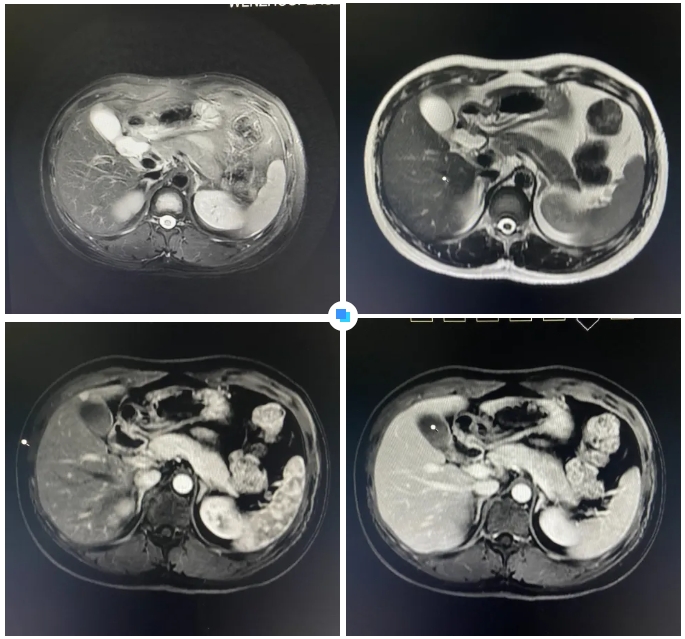

最近,和平國際醫(yī)院影像中心團隊如同“神探般”揪出了隱藏在26歲小伙體內7mm的微小肝癌。

其實,診斷過程中還有一個小插曲:在和平國際醫(yī)院被初步查出疑似小肝癌病灶后,患者馬上前往上海大三甲醫(yī)院進行再次檢查,結果并沒有發(fā)現(xiàn)病灶。

但和平國際醫(yī)院的影像報告引起了三甲醫(yī)院專家的重視。通過將兩家醫(yī)院的影像資料進行對比分析,最終找到了患者肝臟內的7mm病灶。隨后的手術證實,該病灶確實為微小肝癌。

在被問到如何發(fā)現(xiàn)隱藏如此深的病灶時,和平國際醫(yī)院影像中心執(zhí)行主任侯文杰講到,該病灶在平掃T1、T2項都非常不清楚,只有彌散加權的情況下,病灶區(qū)域顯示出輕微的高信號,這一細微線索引起了他的高度關注。

隨后的增強核磁掃描發(fā)現(xiàn),在動脈期病灶顯著強化,而在門脈期明顯減退,這一特征與微小肝癌的表現(xiàn)高度吻合。

“肝癌不可怕,早期發(fā)現(xiàn)是關鍵。”侯文杰主任講到,肝癌的五年生存率較低,但早期的小肝癌一旦發(fā)現(xiàn),預后效果會非常好。磁共振(MR)檢查可以發(fā)現(xiàn)亞厘米級肝癌、乃至癌前不典型增生結節(jié),為臨床醫(yī)生開展腫瘤早期手術切除術或介入等相關外科治療方案提供了精準的影像依據(jù)。